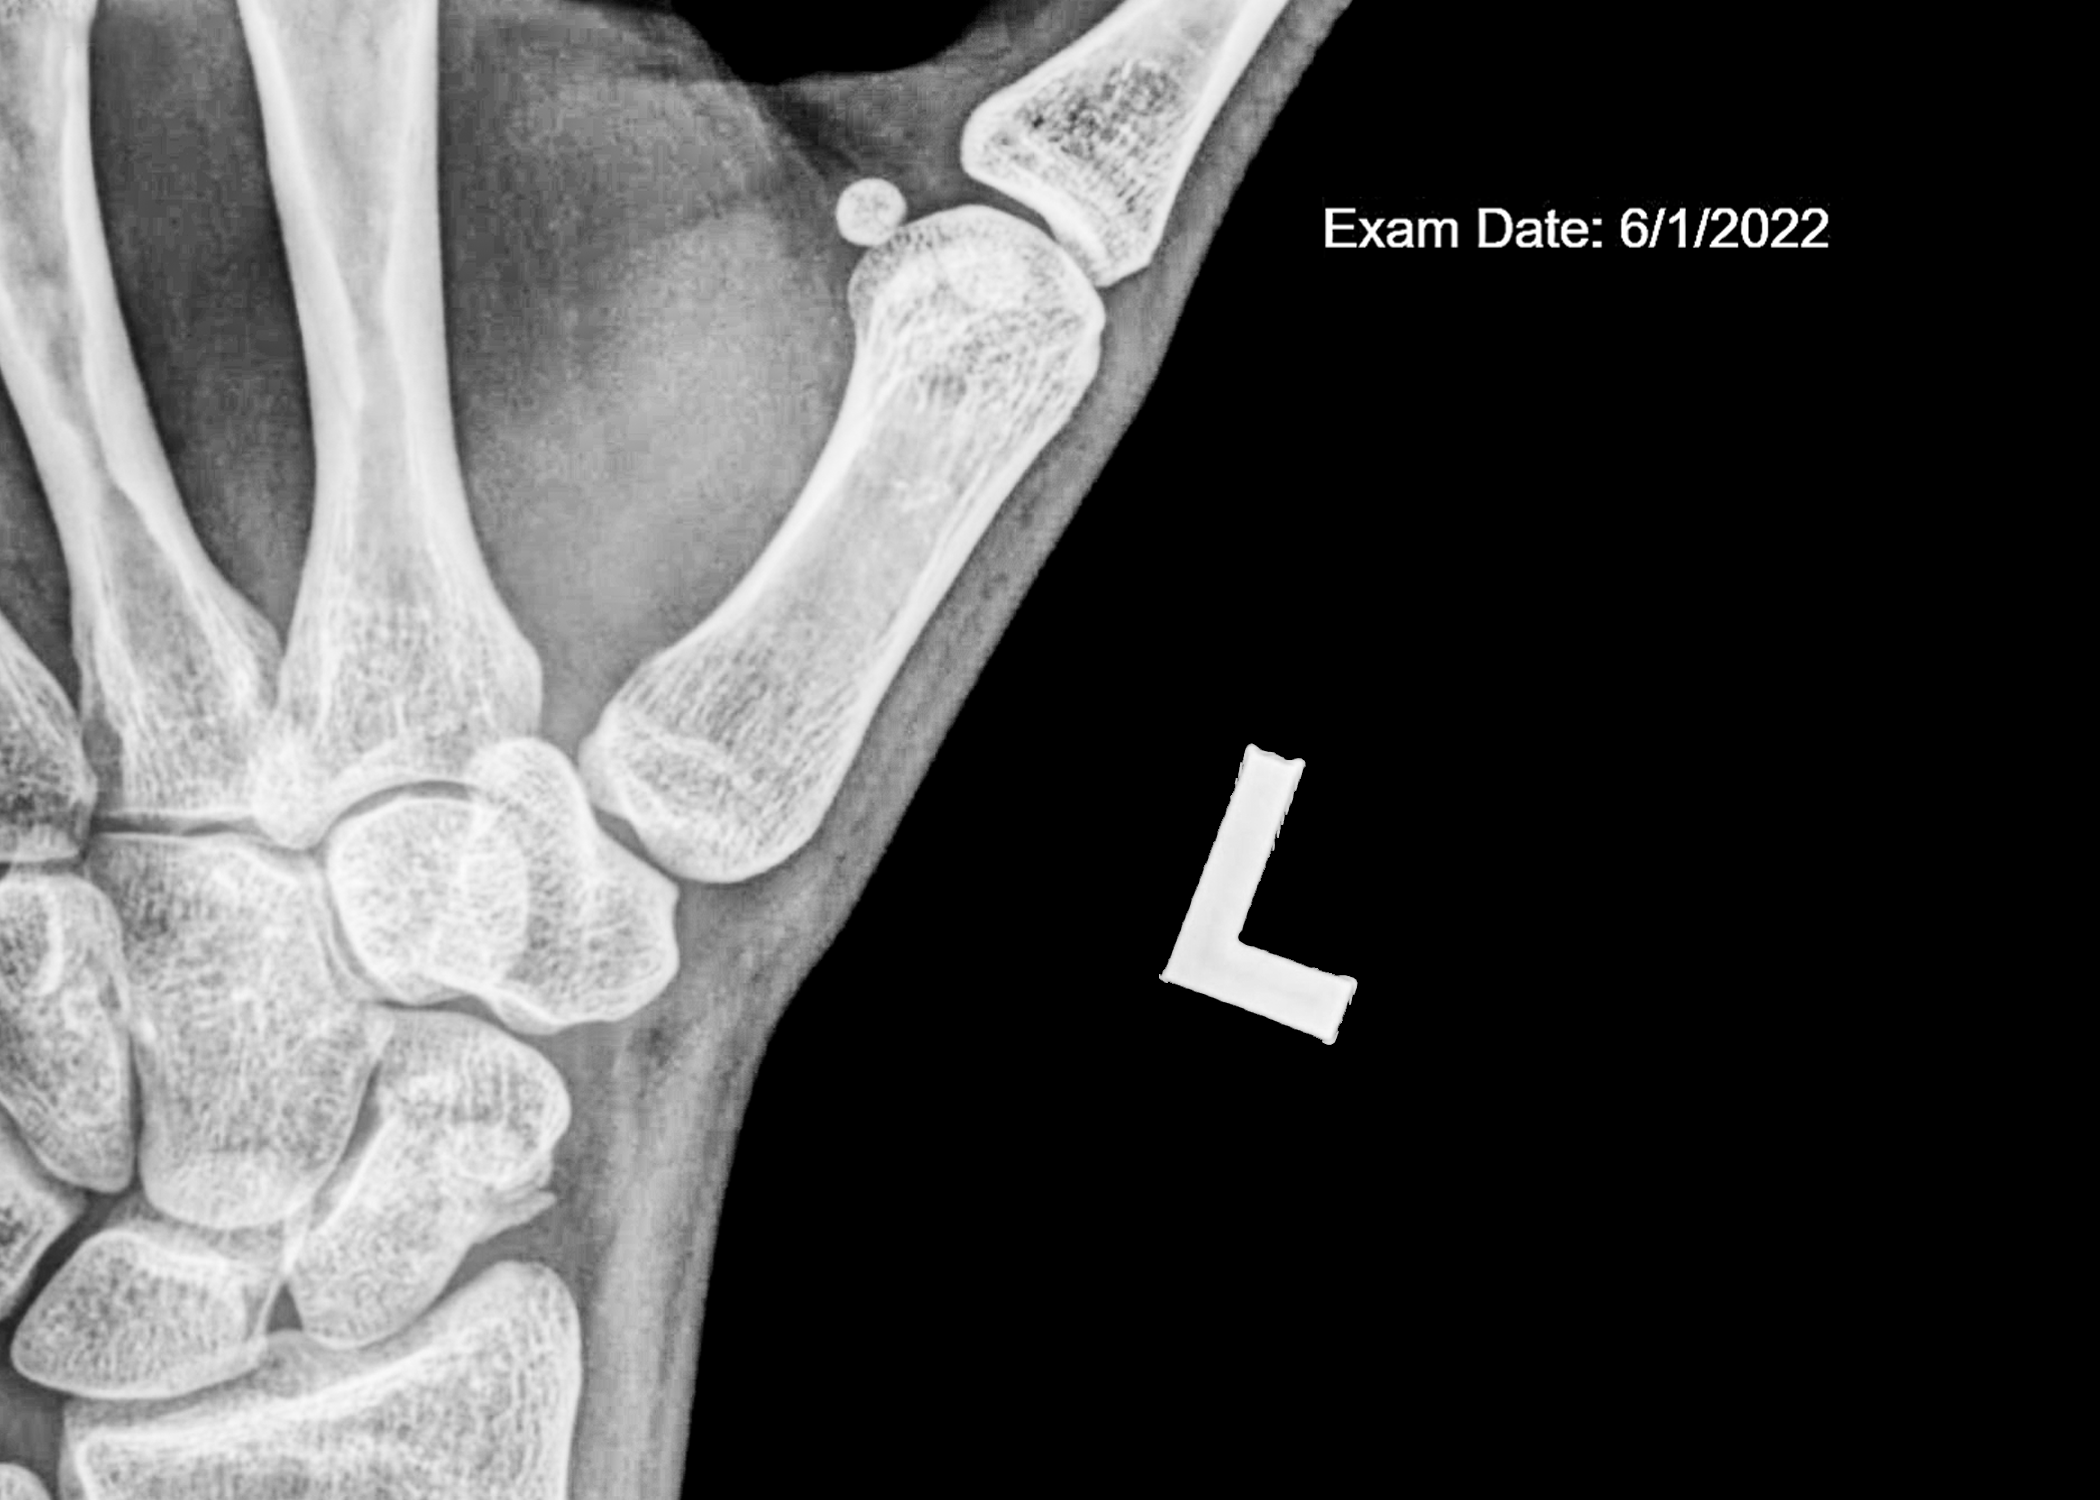

faux flowers X-rays, and tape installation

“Those sounded like terrible memories to have. I wonder if they will ever come back. I hope they don’t” -6/14/2022. Although my memories from the fall never came to me, the aftermath can never be forgotten. More than anything, I wanted to find meaning in my accident.